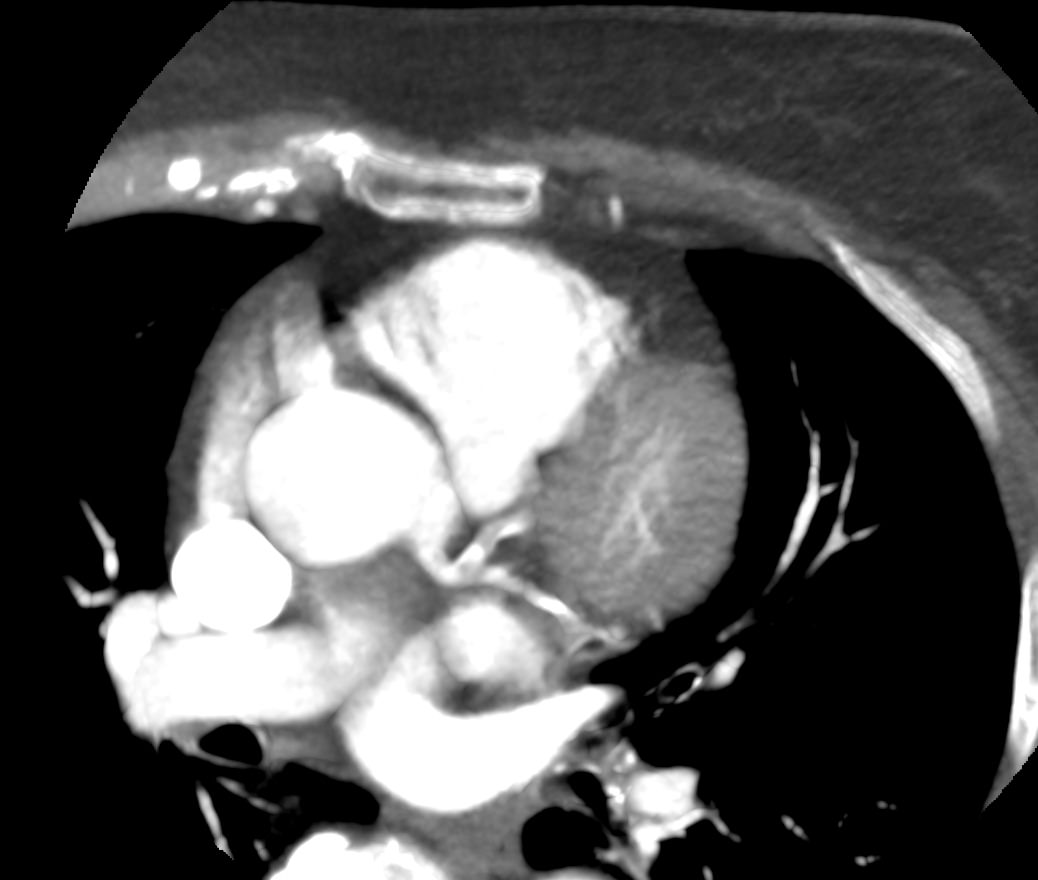

Мультиспиральная КТ сосудов сердца (коронарография) является лучевым методом исследования состояния кровеносных сосудов сердца. Это значит, что для получения изображения сосудов сердца используется рентгеновское излучение.

В нашей клинике КТ-коронарография выполняется на современных мультиспиральных компьютерных томографах последнего поколения TOSHIBA AQUILION. Трубка томографа испускает рентгеновские лучи, непрерывно вращаясь вокруг области исследования. Аппараты оборудованы увеличенным количеством детекторов, которые улавливают сигналы от внутренних органов после прохождения рентгеновских лучей. С помощью цифровых приложений полученные результаты преобразуются в трехмерные изображения сосудистой системы сердца.

Для того, чтобы качественно визуализировать коронарные артерии пациенту внутривенно вводится контрастный препарат на основе йода. Благодаря способности контраста поглощать рентгеновские лучи, коронарные сосуды ярко контрастируют на фоне окружающих тканей. Метод КТ-коронарографии дает информацию о точной локализации стеноза, позволяет судить о степени сужения коронарных артерий, позволяет выявить аномалии развития сосудов сердца, а также оценить состояние установленных в просвет артерий стентов, функционирование шунтов после операции аортокоронарного шунтирования. При этом аппараты обеспечивают минимальную дозу рентгеновского облучения для организма человека.

Мультиспиральная КТ сосудов сердца позволяет оценить анатомические особенности строения коронарных артерий, выявить участки сужения просвета сосудов, изучить структуру атеросклеротической бляшки, выявить кальциноз стенок сосудов и клапанов сердца.